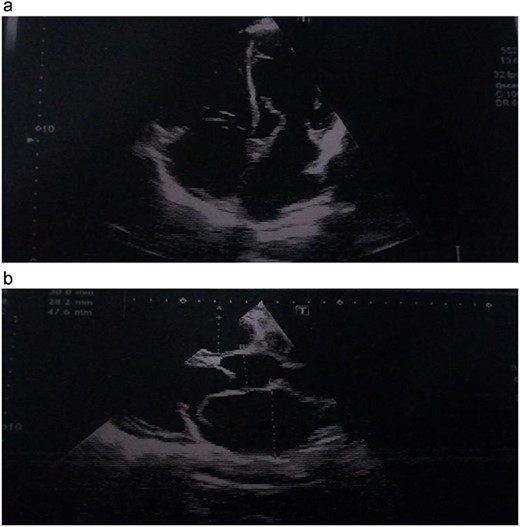

He was dyspneic, not pale and afebrile. He had bilateral pitting pedal edema up to the knees. Pulse rate was 102 regular non-collapsing, and blood pressure was 96/75 mmHg. The precordium was active, with the apex beat located in the sixth left inter-coastal space anterior axillary line. The first and second heart sounds were present, with an apical pan systolic murmur, which radiated to the left axilla. The respiratory rate was 20 cycles/min, with bi-basal crepitations on auscultation. The abdomen and other systems were normal. The Chest X-ray showed cardiomegaly with pulmonary plethora. The echocardiography (ECG) (Fig. 1) showed sinus tachycardia with inverted T-waves in the anterolateral leads. The ECG (Fig. 2a and b) showed normal global and segmental contractility with an ejection fraction of 75%. There was moderate dilation of the left atrium, with severe mitral regurgitation secondary to anterior mitral valve prolapse caused by rupture of the anterolateral papillary muscle. The intraoperative findings (Figs 3a, b and 4) were a deficient left hemi-pericardium, and rupture of the anterolateral papillary muscle. He had mitral valve replacement with a mechanical prosthetic valve. The postoperative period was uneventful, and the patient was discharged from the hospital after 9 days.

(a, b) Echocardiographic picture showing the avulsed papillary muscle.